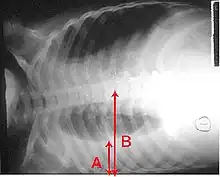

Majoritatea bacteriilor pătrund în plămâni prin aspirarea unor organisme mici, aflate în gât sau nas.[15] Jumătate dintre oamenii normali manifestă astfel de aspirații în timpul somnului.[22] În timp ce în gât se găsesc întotdeauna bacterii, cele potențial infecțioase sunt prezente numai în anumite momente și condiții.[22] Câteva tipuri de bacterii, cum ar fi Mycobacterium tuberculosis și Legionella pneumophila, pot ajunge în plămâni prin intermediul unor picături mici contaminate, purtate de aer.[15] Bacteriile se pot răspândi prin sânge.[16] Odată ajunse în plămâni, bacteriile pot invada spațiile dintre celule și dintre alveole, unde macrofagele și neutrofilele (celulele albe din sânge cu rol defensiv) încearcă să anihileze bacteriile.[36] De asemenea, neutrofilele eliberează citokine, determinând astfel o activare generală a sistemului imunitar.[37] Acest lucru duce la febră, frisoane și oboseală, întâlnite în pneumonia bacteriană.[37] Neutrofilele, bacteriile și lichidul din vasele de sânge înconjurătoare umplu alveolele, rezultând acumularea ce apare la radiografie.[38]

Radiografiile pot clasifica pneumonia drept pneumonie lobară, bronhopneumonie (cunoscută drept pneumonie lobulară), și pneumonie interstițială.[44] Pneumonia bacteriană, existentă în comunitate, prezintă de regulă consolidarea pulmonară a unui lob pulmonar, fiind cunoscută drept pneumonie lobară.[24] Cu toate acestea, rezultatele pot varia, iar alte caracteristici sunt obișnuite în alte tipuri de pneumonie.[24] Pneumonia de aspirație poate prezenta opacități bilaterale mai ales la baza plămânilor și pe partea dreaptă.[24] Este posibil ca în unele cazuri radiografiile pneumoniei virale să pară normale, să aibă un aspect hiper-inflamat sau să pară similare pneumoniei bacteriene cu consolidare lobară.[24] Este posibil ca în stadiile incipiente ale bolii să nu existe semne depistabile radiologic, mai ales în cazul deshidratării; sau pot fi dificil de interpretat în cazul persoanelor obeze sau care au antecedente de afecțiuni pulmonare.[15] O tomografie computerizată poate oferi informații suplimentare în cazurile incerte.[24]